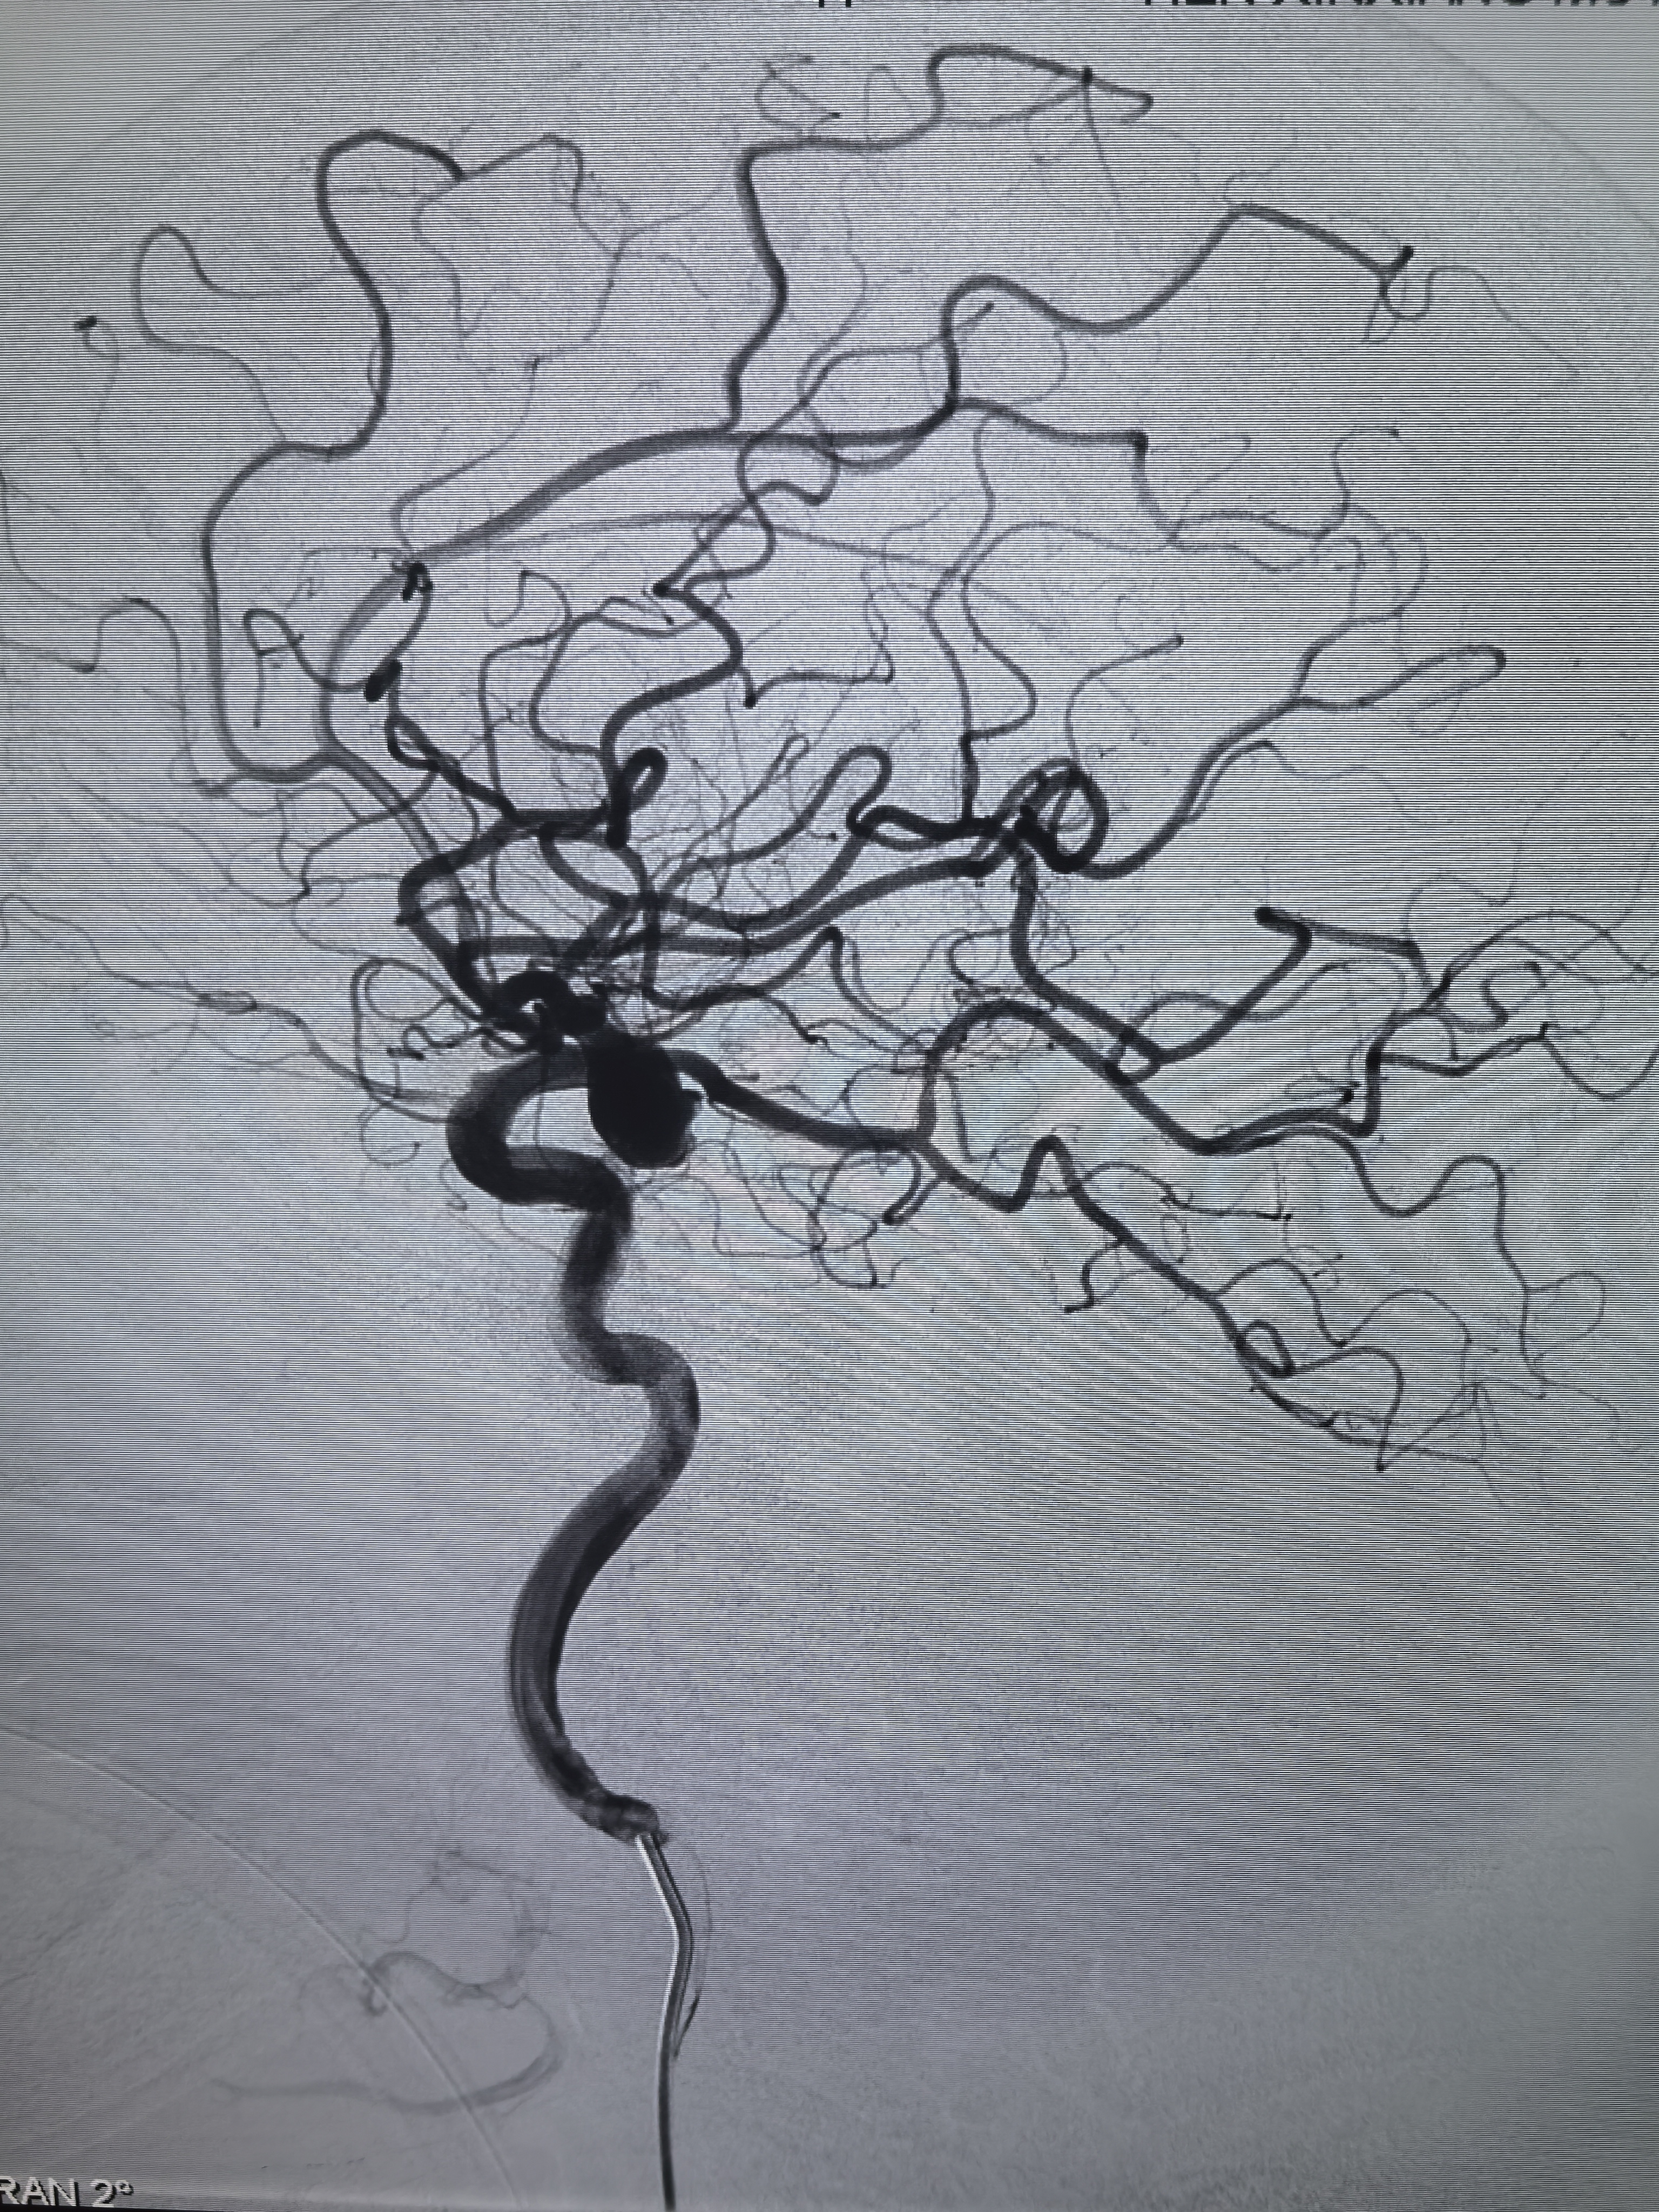

术后侧位造影,后交通动脉血流还是减少!

术后正位造影!

术后椎动脉造影左侧大脑后动脉显影良好!